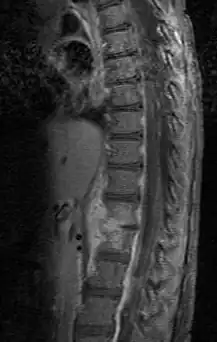

Diagnosis is usually apparent on MRI, although plain X-rays and CT examinations can be suggestive. The MRI will reveal air changes in the disc and possibly even external involvement involving the bone or epidural regions. A biopsy may be performed and helps with diagnosis in some cases but often an organism is not obtained. C-reactive protein levels and ESR levels will be elevated and are useful for treatment. The white blood cell count may be normal.[5][6]